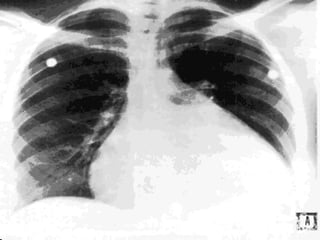

Pulmonary Edema The most severe manifestation of Left Heart Failure  Fluid leak into the pulmonary interstitial spaces (Pulmonary congestion/edema) Hypoxia and poor 02 exchange

PULMONARY CONGESTION & RESPIRATORY SYMPTOMS: Result of dilatation & increasing left ventricular end diastolic pressure, left atrial pressure & capillary pressures Results to pulmonary vascular congestion & symptoms associated with cough with blood tinged sputum

Pulmonary Edema Themost severe manifestation of Left Heart Failure Fluid leak into the pulmonary interstitial spaces (Pulmonary congestion/edema) Hypoxia and poor 02 exchange

PULMONARY CONGESTION &RESPIRATORY SYMPTOMS: Result of dilatation & increasing left ventricular end diastolic pressure, left atrial pressure & capillary pressures Results to pulmonary vascular congestion & symptoms associated with cough with blood tinged sputum